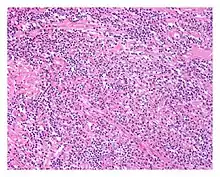

| Low power view of IgG4-related prostatitis. The prostatic stroma shows a dense inflammatory infiltrate and fibrosis (H&E, 100x) | |